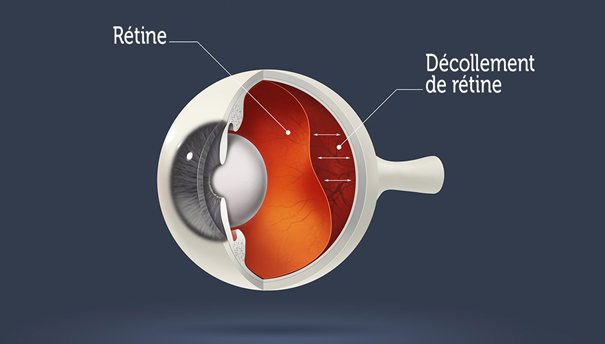

decollement retine photo Décollement de rétine

www.retine-chirurgie-nantes.frDécollement De Rétine - Ophtalmologie L’Union

www.retine-chirurgie-nantes.frDécollement De Rétine - Ophtalmologie L’Union